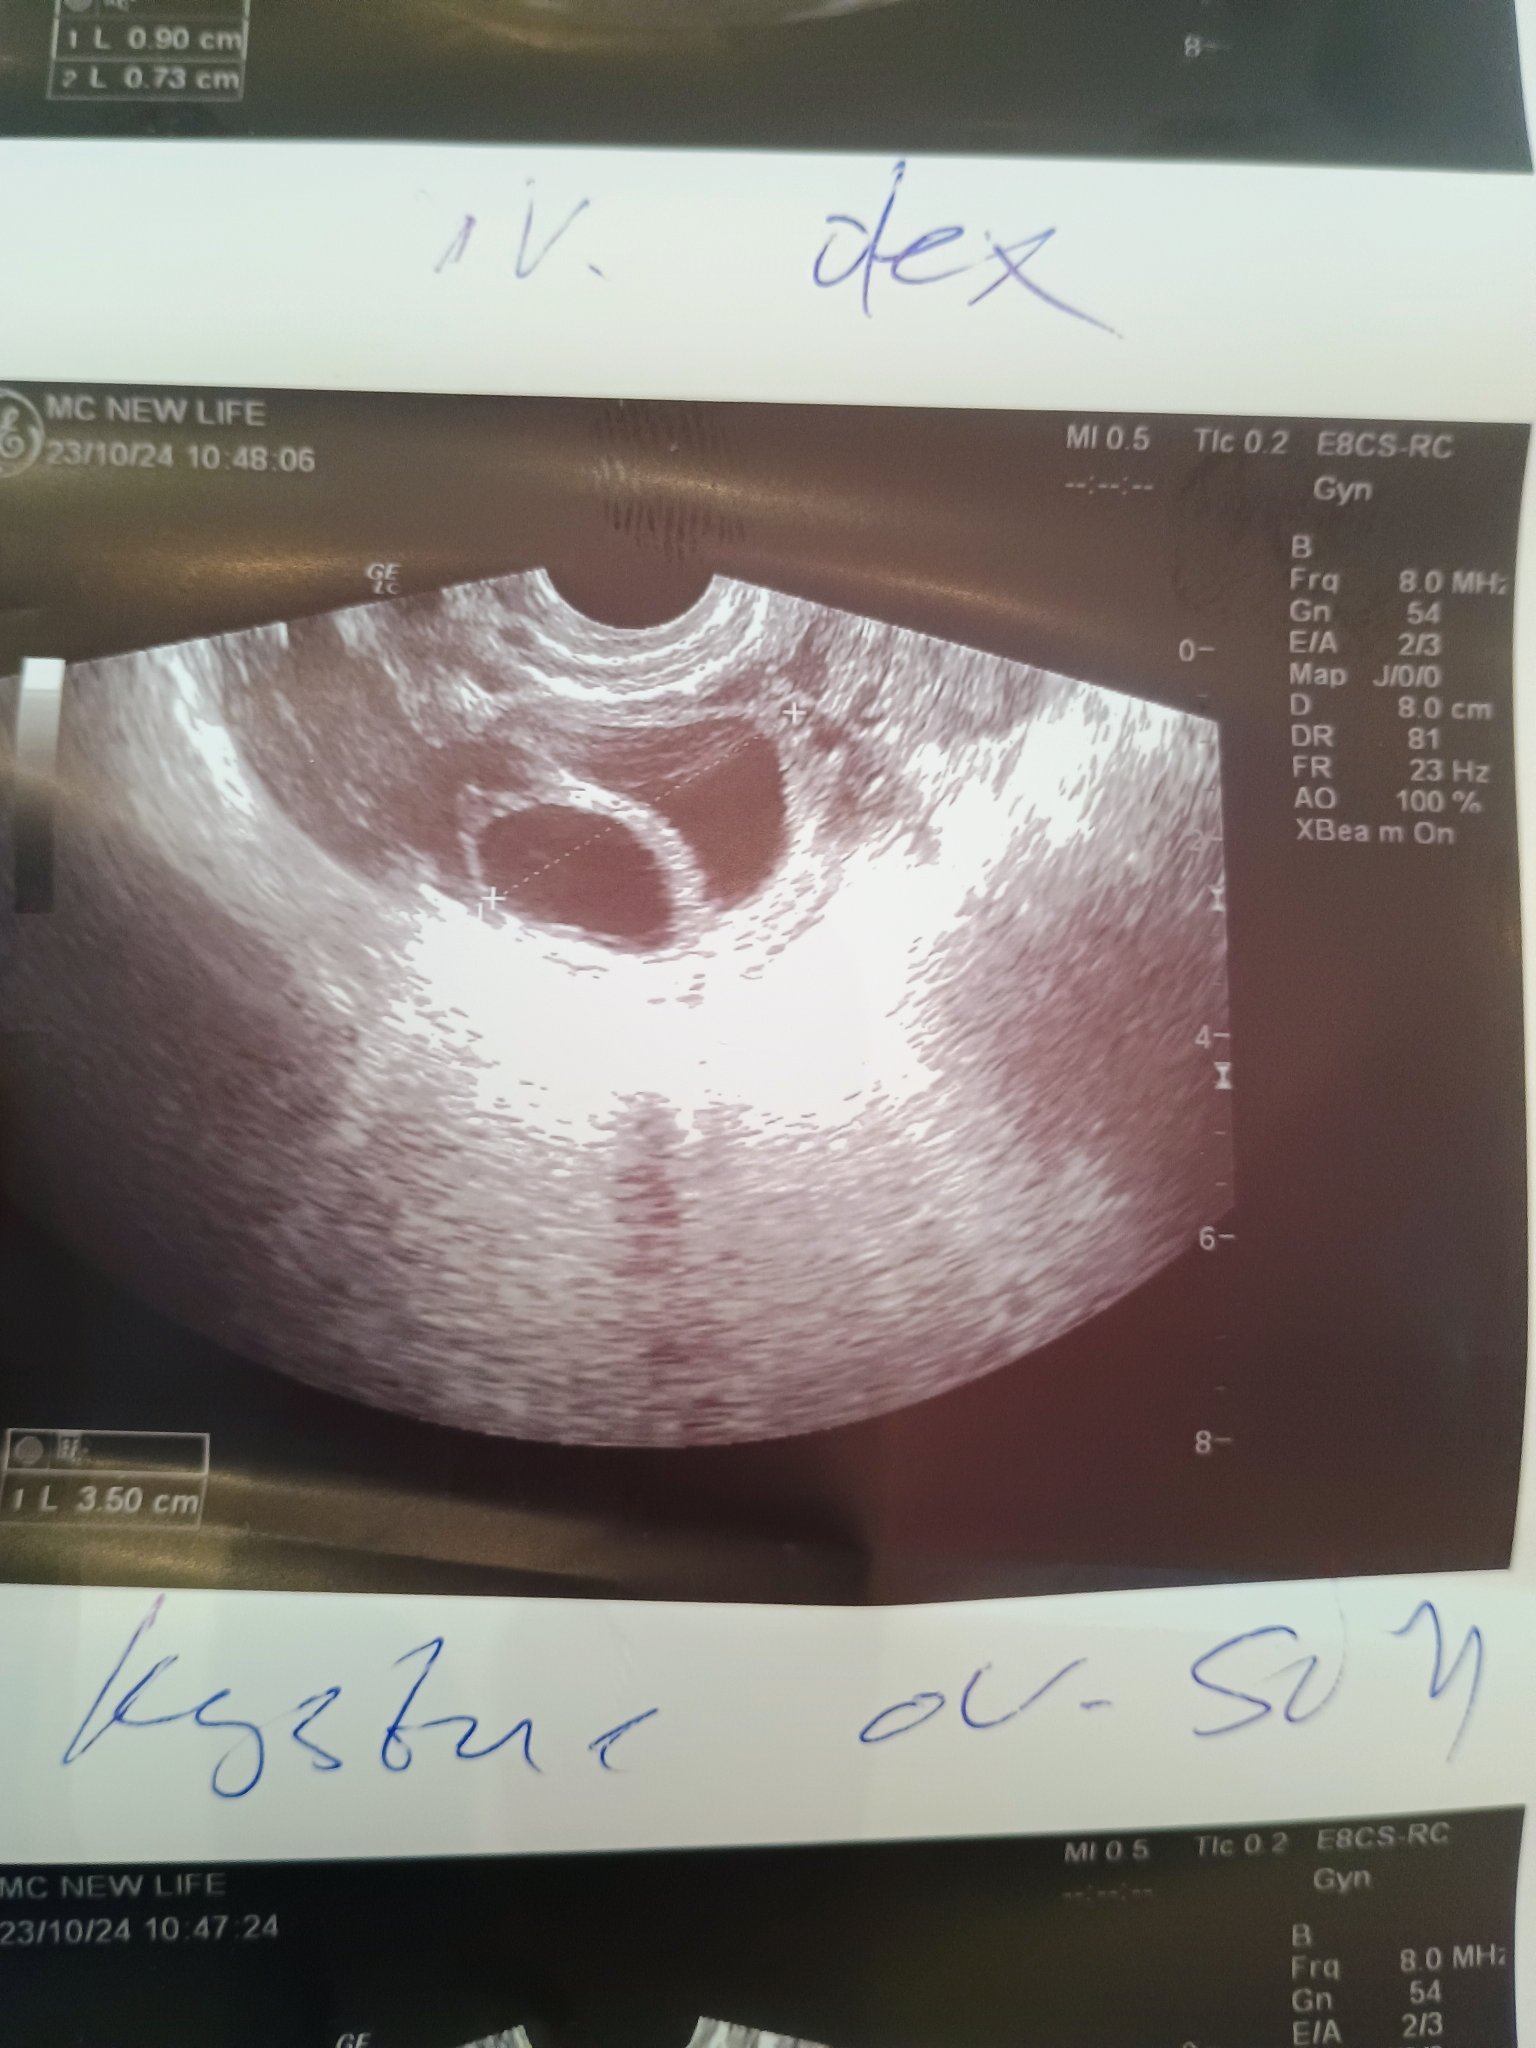

Този ми говори за операция . Каква операция ? Ще ида на още 1 мнение . Не може да разграничи ДФ и киста на яйчника . Ендуметриума е 1 см.Теста за О ми е положителен  днес . Не знам какво става ,много съм объркана .н